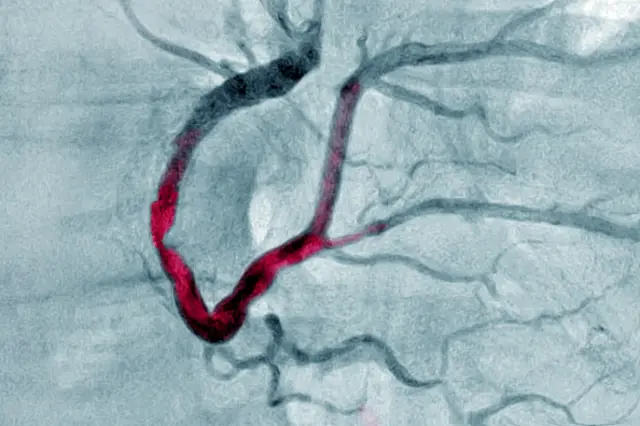

పల్మనరీ యాంజీయోగ్రామ్ చేస్తే త్రాంబస్ (రక్తనాళంలో రక్తం గడ్డ కట్టుకోవడం) ఉన్నట్లు తేలింది. అంత చిన్న వయసులో స్టంట్ వేయాలంటే బాధగా అనిపించిందని వైద్యులు చెప్పారు.

ఇదే విషయంపై డాక్టర్ రమాకుమారి మాట్లాడుతూ డయాబెటిస్, బీపీ, హైపర్ టెన్షన్ ఫెయిల్యూర్ను ఇంకా ఎక్కువ చేస్తాయి. ఎకో, ఈసీజీ, కార్డియాక్ ఎంఆర్ఐ, పల్మనరీ యాంజియోగ్రామ్ చేయించుకోవాలి. ఇవన్నీ చేయించుకున్నాకే జిమ్ వంటి వాటికి వెళ్లడం మేలు’’ అని చెప్పారు.